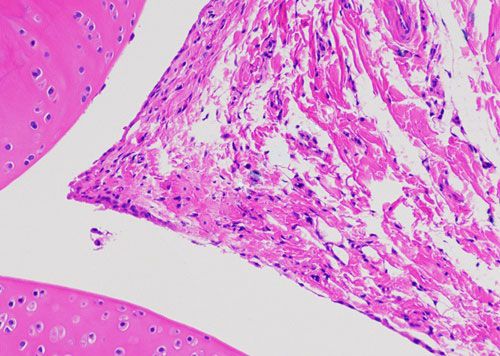

實驗結(jié)果展示:

正置顯微鏡型號:NIKON Eclipse ci;軟件:NIS_F_Ver43000_64bit_E;成像系統(tǒng):NIKON digital sight DS-FI2。可選擇 20×、40×、100×、200×和400×不同放大倍數(shù)。

(3)實驗結(jié)果:實驗結(jié)果:圖片×6(常規(guī)同視野下200×3、400×3)

(5) 如無拍照要求,即按常見的部位拍,例如:肝中央靜脈、腦皮層海馬、腎小球等,特殊染色以及免疫組化陽性部位。